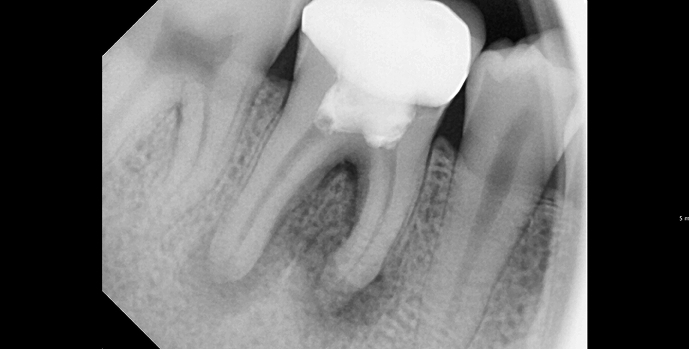

BEFORE & AFTER

• 20대 남성 | 치근단병소 | 재신경치료 | 치료기간 4주

Before 2025.04.30

After 2025.05.29

X-ray(필요 시 3D CT)로 염증 범위와 근관 형태를 확인하고, 통증 원인을 정밀 평가합니다.